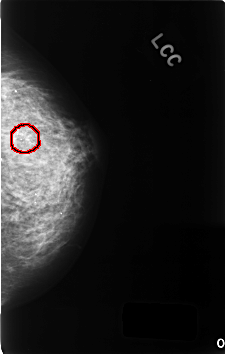

FILE: C_0344_1.LEFT_CC.OVERLAY

TOTAL_ABNORMALITIES 1

ABNORMALITY 1

LESION_TYPE CALCIFICATION TYPE FINE_LINEAR_BRANCHING DISTRIBUTION CLUSTERED

ASSESSMENT 5

SUBTLETY 5

PATHOLOGY MALIGNANT

TOTAL_OUTLINES 1

BOUNDARY